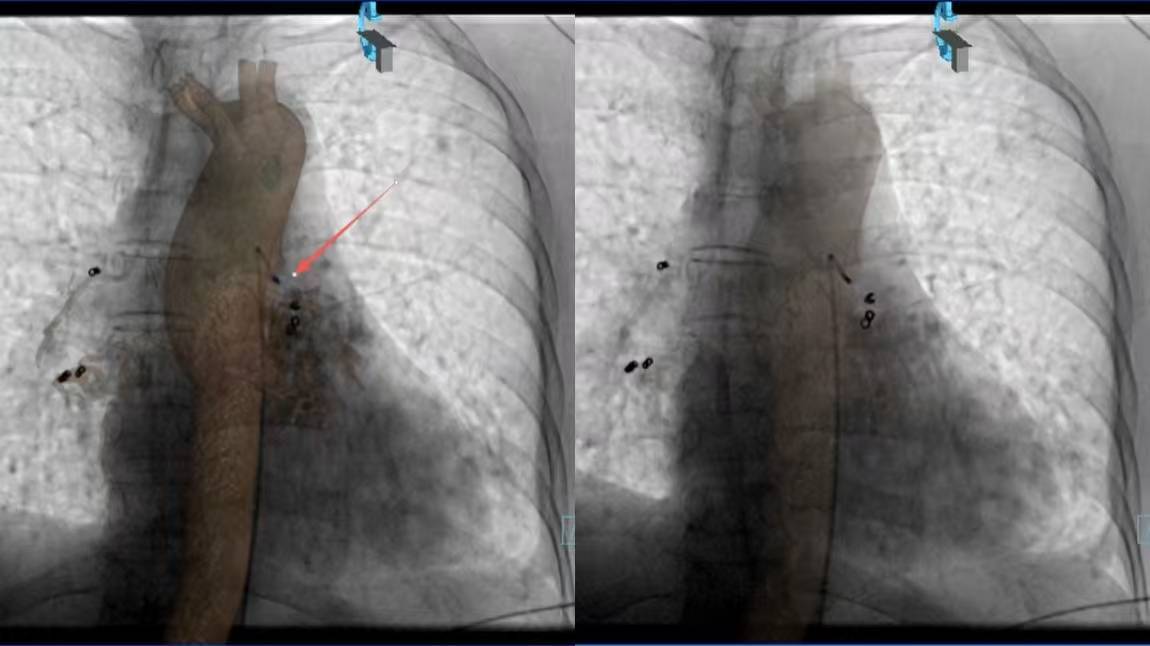

术前CTA与术中DSA影像精准配准,3D Fusion技术让迂曲血管立体呈现,Overlay技术将血管走形叠加在实时画面上——原本“盲探”的出血点,瞬间“一眼锁定”。微导管在导航引导下快速且精准到达靶血管,快速注入栓塞剂顺利止血。从麻醉到手术结束,仅用45分钟,较传统手术缩短近2小时。

术前造影 (L) (西安大兴医院) 术后造影(L)

术前造影(R) 术后造影(R)